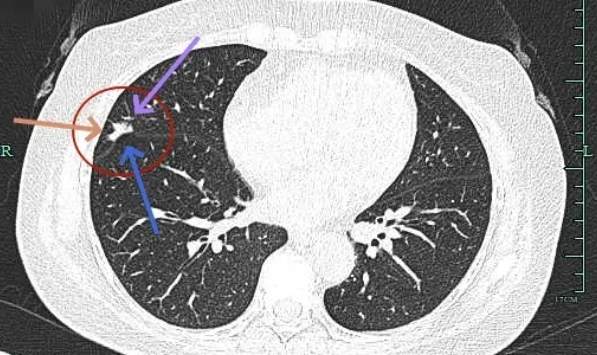

叶间胸膜受牵拉凹陷,有微小血管进入,表面毛刺与不平。

实性成分也有明显毛刺,叶间裂牵拉明显,表面有分叶征。

边缘紧贴叶间裂,密度较高。